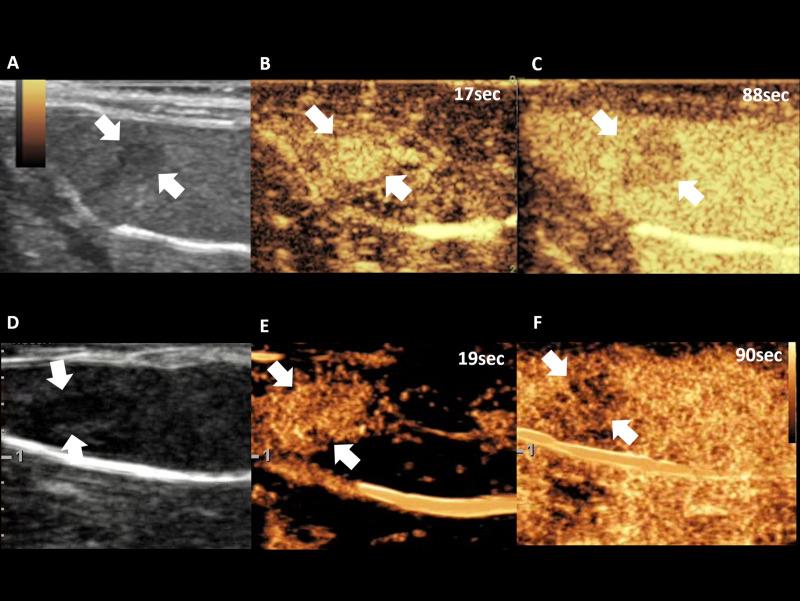

应用超声造影监测肝细胞癌大鼠模型中靶向治疗的疗效:重点探讨扫描仪间和操作者间的可重复性。

Therapeutic response monitoring after targeted therapy in an orthotopic rat model of hepatocellular carcinoma using contrast-enhanced ultrasound: Focusing on inter-scanner, and inter-operator reproducibility.

To assess therapeutic response monitoring after targeted therapy in an orthotopic rat model of hepatocellular carcinoma (HCC) using CEUS with focusing on inter-scanner and inter-operator reproducibility.

MATERIALS AND METHODS

For reproducibility, CEUS was performed using two different US scanners by two operators in sixteen rat models of HCC. Using perfusion analysis software (VueBox ®), eleven parameters were collected, and intra-class correlation coefficient (ICC) was used to analyze reproducibility. Then seventeen rat models of HCC were divided into treatment group (n = 8, 30 mg/kg/day sorafenib for five days) and control group (n = 9). CEUS was performed at baseline and 14 days after first treatment, and changes of perfusion parameters were analyzed.

RESULTS

In treatment group, CEUS perfusion parameters showed a significant change. The peak enhancement (PE, 2.50 x103±1.68 x103 vs 5.55x102±4.65x102, p = 0.010) and wash-in and wash out AUC (WiWoAUC, 1.07x105±6.48 x104 vs 2.65x104±2.25x104, p = 0.009) had significantly decreased two weeks after treatment. On the contrary, control group did not show a significant change, including PE (1.15 x103±7.53x102 vs 9.43x102± 7.81 x102, p = 0.632) and WiWoAUC (5.09 x104±3.25x104 vs 5.92 x104±3.20x104, p = 0.646). For reproducibility, the various degrees of inter-scanner reproducibility were from poor to good (ICC: <0.01-0.63). However, inter-operator reproducibility of important perfusion parameters, including WiAUC, WoAUC, and WiWoAUC, ranged from fair to excellent (ICC: 0.59-0.93) in a different scanner.

CONCLUSION

Our results suggest that CEUS is useful for assessment of the treatment response after targeted therapy and with fair to excellent inter-operator reproducibility.